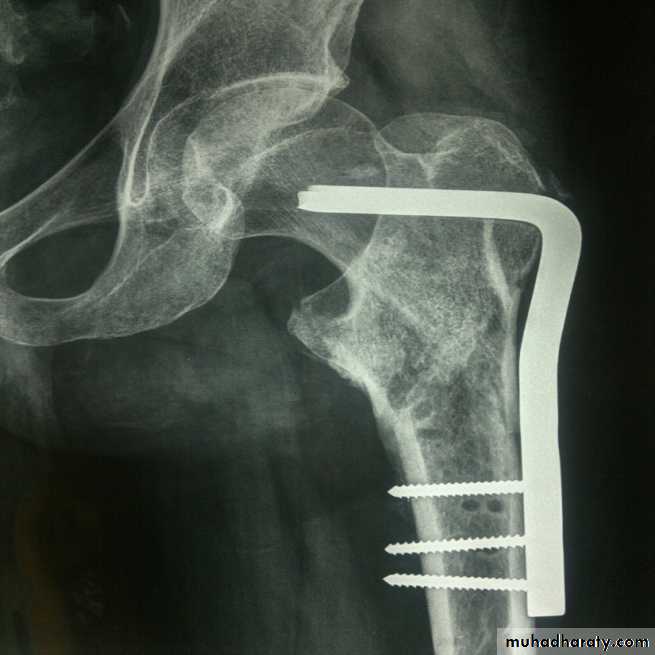

The fracture is fixed with an angled device – preferably a sliding screw in conjunction with a plate (dynamic hip screw) or

intramedullary nail. or

95 degree screw-plate (L-Plate)

Dynamic hip screw

L-plate (fixed angle plate)